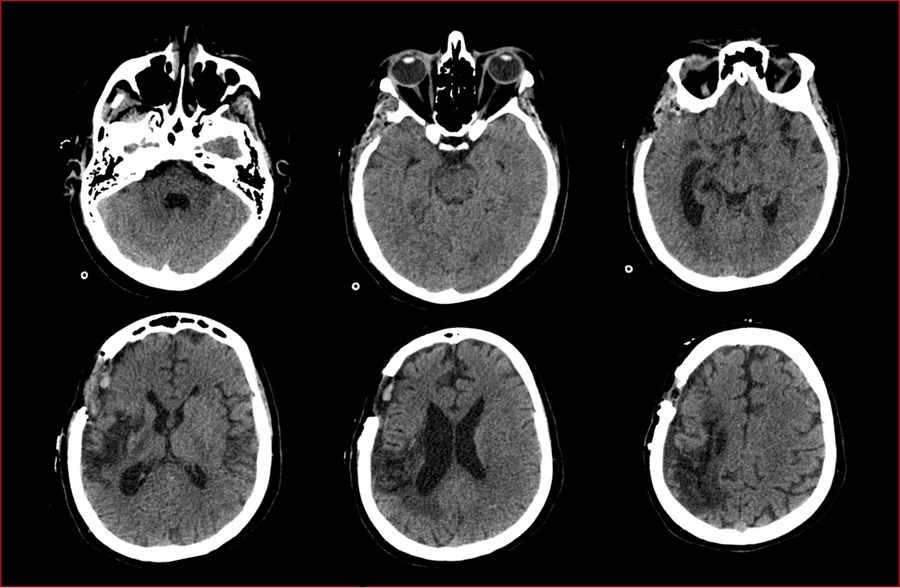

This case concerns a 35-year-old female patient presenting worsening neurological signs and symptoms marked by a three  year history of transient episodes of visual loss in the right eye. For  two of those years, the patient suffered a complete hemiparesis, and one year of right lip rhyme deviation. For ten months, she also experienced an incomplete left hemiparesis.

The patient had previously been diagnosed with Takayasu‘s arteritis and was being treated with pulse therapy and methotrexate. In addition, the patient had a medical history of systemic arterial hypertension, diabetes, dyslipidemia, and depression.

Neurological examination

The patient was fully conscious and well-oriented, with left nasolabial fold erasure and rightward rhyme deviation. She presented a left hemiparesis with brachial predominance, as well as tactile and painful hypoesthesias in the left lower limb, and allodynia in the right upper limb.

Diagnosis

The patient was diagnosed with a stroke in the region supplied by the right middle cerebral artery caused by Moyamoya disease.

Catheter angiography was performed with the following findings:

• Occlusion at the proximal third of the cervical segment of the right internal carotid artery

• Stenosis of the supraclinoid segment of the left internal carotid artery

• Proximal stenosis of the anterior and middle cerebral arteries with collateral «smoke puff» vessels, which are characteristic findings of moyamoya disease

• Collateral circulation from the internal maxillary artery to the ipsilateral carotid territory

• Collateral irrigation of the carotid territory from the posterior circulation through a patent posterior communicating artery

A DSA (digital subtraction angiography) was performed pre-operatively to assess the occlusions of the internal and external

carotid arteries, as well as stenosis of the arteries and the feeding and draining blood vessels of the arteriovenous malformation, as

shown in the images below.

Post-surgery assessment

The postoperative CT scan showed no signs of postoperative complications. The presurgical area of ischemia in the territory the right MCA was also observed. The patient showed no additional postoperative neurological deficits and was discharged three days post-surgery.